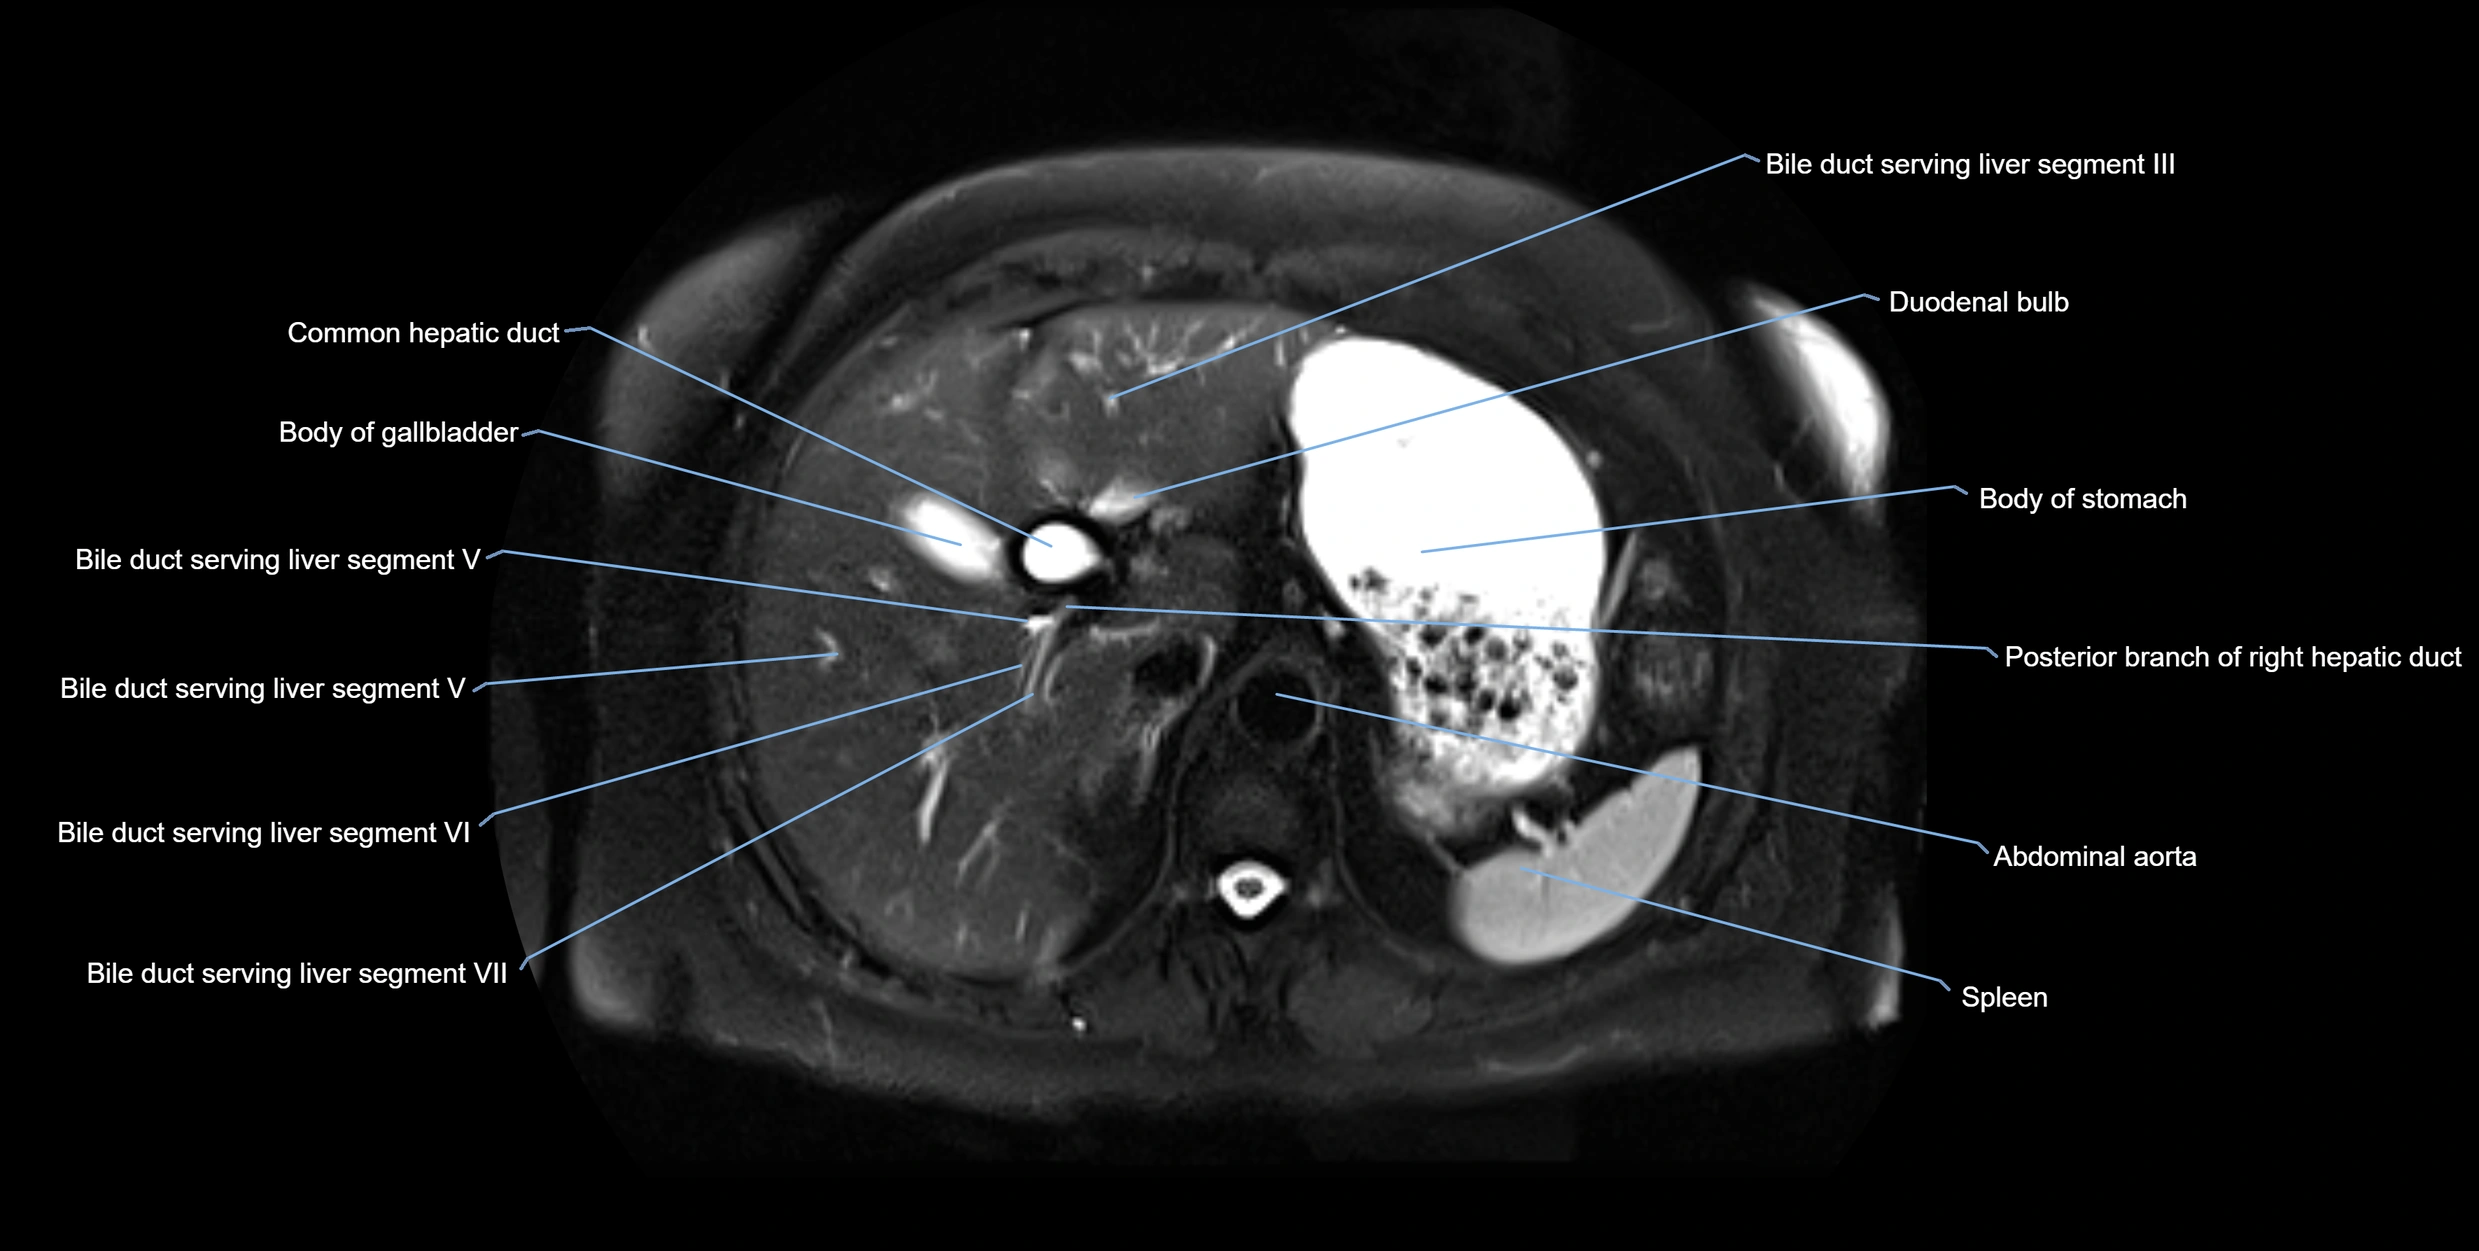

MRI image

image